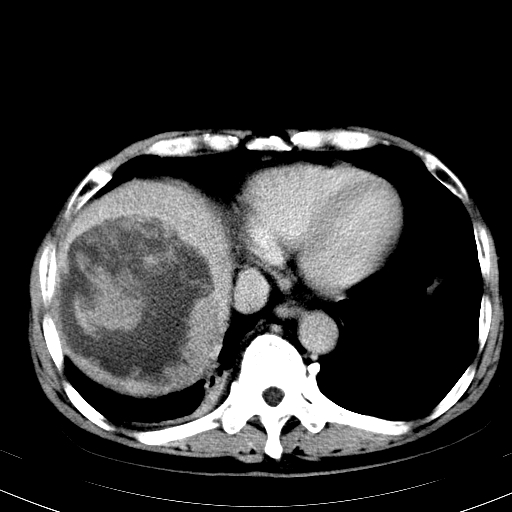

间叶源性肿瘤,血管肉瘤.

以下是引用zjzjr在2008-6-24 11:13:00的发言:[br]间叶源性肿瘤,血管肉瘤.